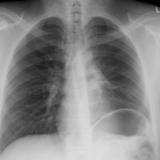

LUL Collapse Case 1 PA

Date: 02/19/2004

Views: 5531